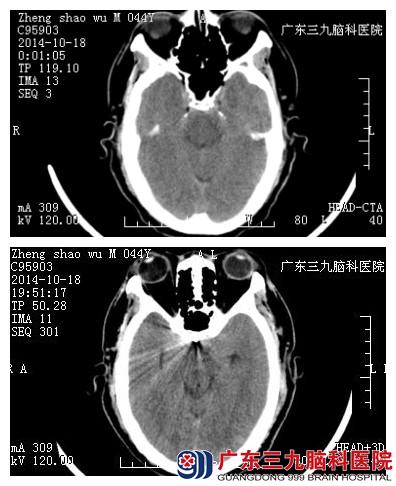

郑先生,44岁,因突发肢体乏力,伴随头痛、头晕症状,前额疼痛尤为严重,呈剧烈样,急去附近医院查头颅,CT结果示:蛛网膜下腔出血,给予脱水降颅压等对症处理,症状稍好转后,急转入广东三九脑科医院。

查体,郑先生神志清楚,精神可,能自动睁眼。入院行辅助检查,CTA示:前交通动脉瘤。诊断:1.蛛网膜下腔出血;2、前交通动脉瘤;考虑前交通动脉瘤破裂。检查无明显手术禁忌症,神经外三科于2014年10月18日在全麻下为其行“前交通动脉瘤介入栓塞术”。术中顺利,术后给予防治脑血管痉挛、抑制胃酸分泌、活血化瘀等对症治疗。经住院17天,郑先生病情好转出院。